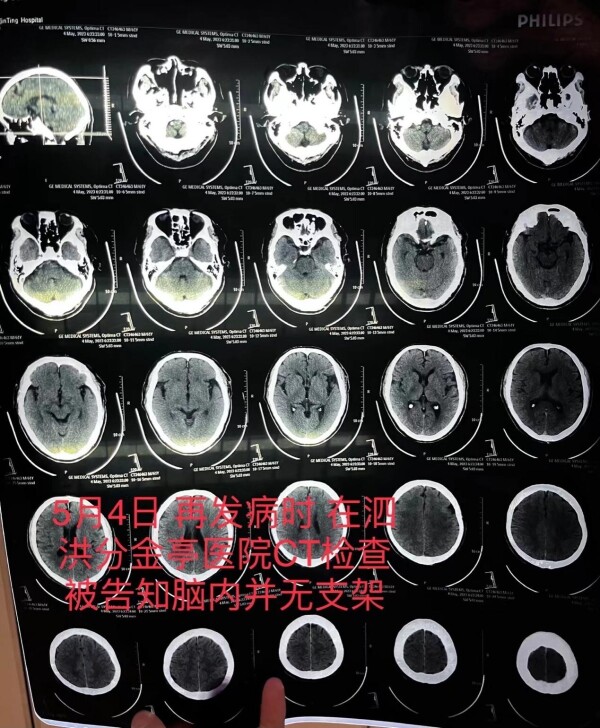

5月4日,朱老汉突发严重脑梗。他先被救护车送至江苏省宿迁市泗洪县分金亭医院抢救。令家属没想到的是,当时的CT检查发现,其颅内段部分动脉已严重堵闭,同时未发现此前植有支架。“我们当时不相信这个检查结果,认为这是小医院,可能检查不出来,所以我们决定转送到之前的医院。”朱先生说,朱老汉又被转入宿迁第一人民医院,曾作为主刀医生的齐某此时才承认,之前未能在患者颅内血管成功植入支架。

朱老汉在泗洪县分金亭医院的CT检查报告,显示颅内并无支架。朱先生供图